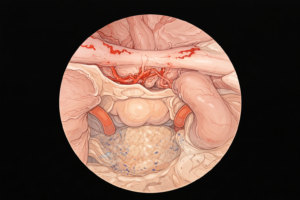

Cirurgia endoscópica da hipófise

Quando indicada, a cirurgia é realizada, na maioria dos casos, por via endonasal endoscópica, ou seja, através do nariz, sem cortes externos.

Essa técnica permite:

- Acesso direto à hipófise

- Menor manipulação do cérebro

- Recuperação mais rápida

- Menor tempo de internação

A indicação cirúrgica é sempre individualizada e baseada em critérios clínicos e radiológicos.